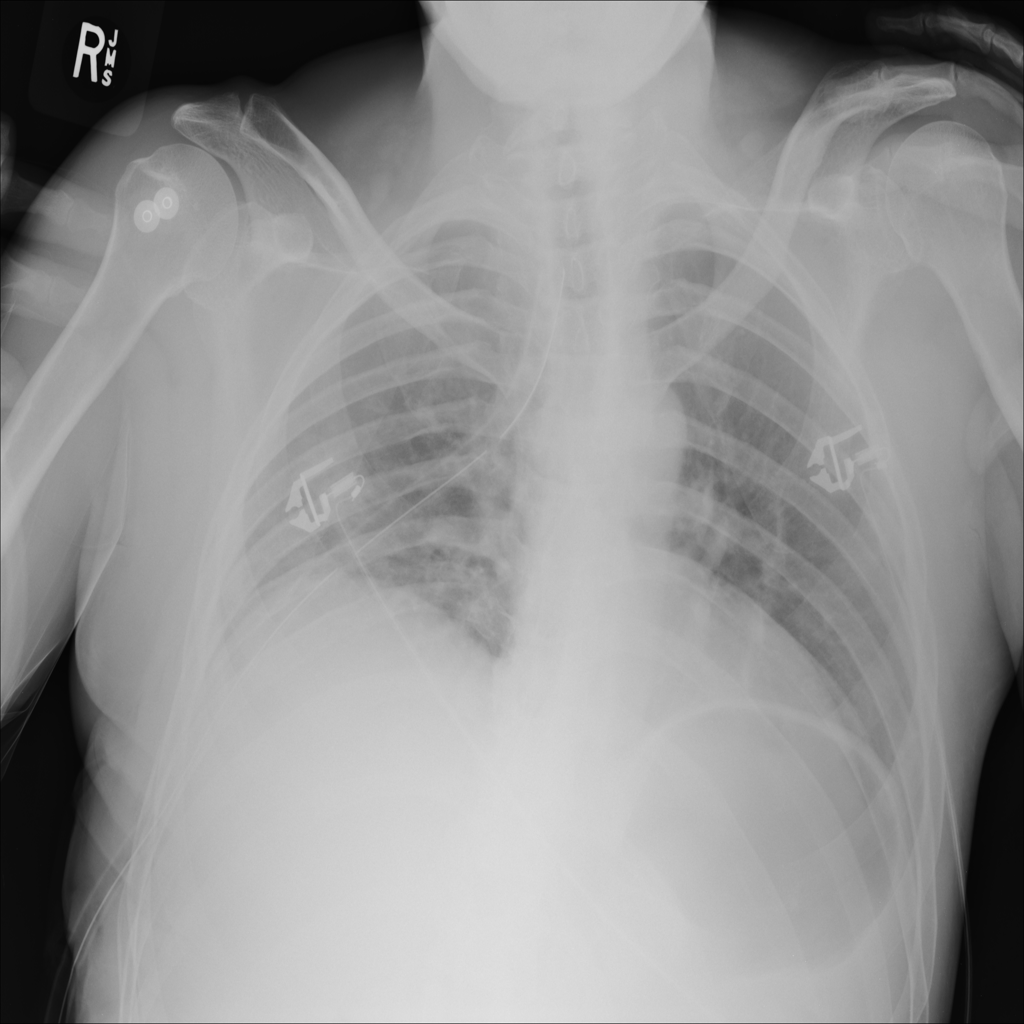

PAT-0E82 · IMG-000Emphysema

PAT-0E82 · IMG-000

AP